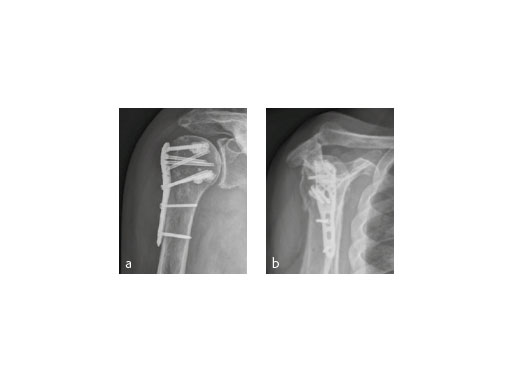

The X-ray review at 3 months after surgery showed an anatomic reduction of the fracture, nicely formatted augmentation, no secondary loss of reduction, and range of motion of the arm reaching the horizontal plane (Fig 7).

ORIF of proximal humeral fractures using an augmentation technique in addition to the PHILOS seems to be a promising concept. Varus-displaced fractures in osteopenic bone situations of the elderly seem to particularly profit from this technique. Up till now we have had no intraarticular misplacement of the cement and no secondary loss of reduction in these challenging fracture types.